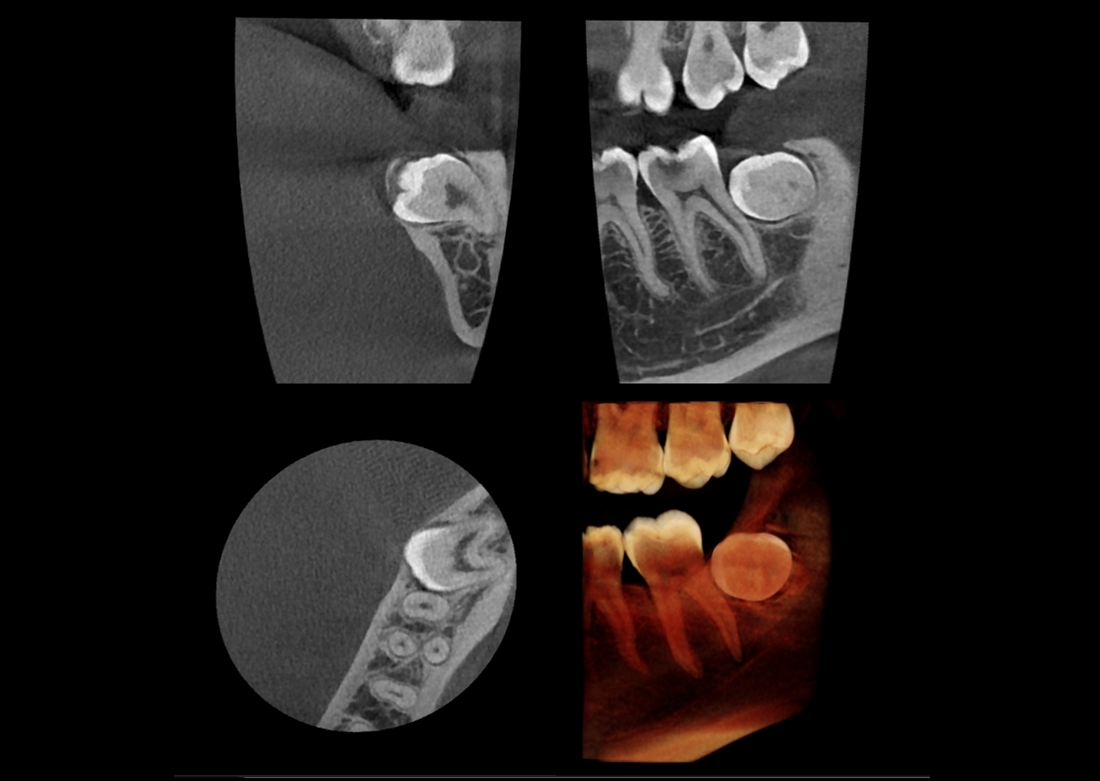

The Papaya 3D Premium/Ultra is the newest generation in a long line of Genoray products designed to produce accurate diagnostic images with wider treatment applications including implants, endo, ortho, airway, TMJ, and orthognathic surgeries. Optimized acquisition PC/Monitor/Accessories, model scan/STL converter, and perpetually licensed software suites included.

- Papaya 3D Premium CBCT: Min 4x5 to Max 16x14 FOV

- Papaya 3D Ultra CBCT: Min 4x5 to Max 23x24* FOV